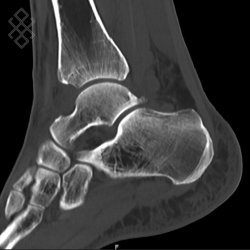

Scanner de la Cheville